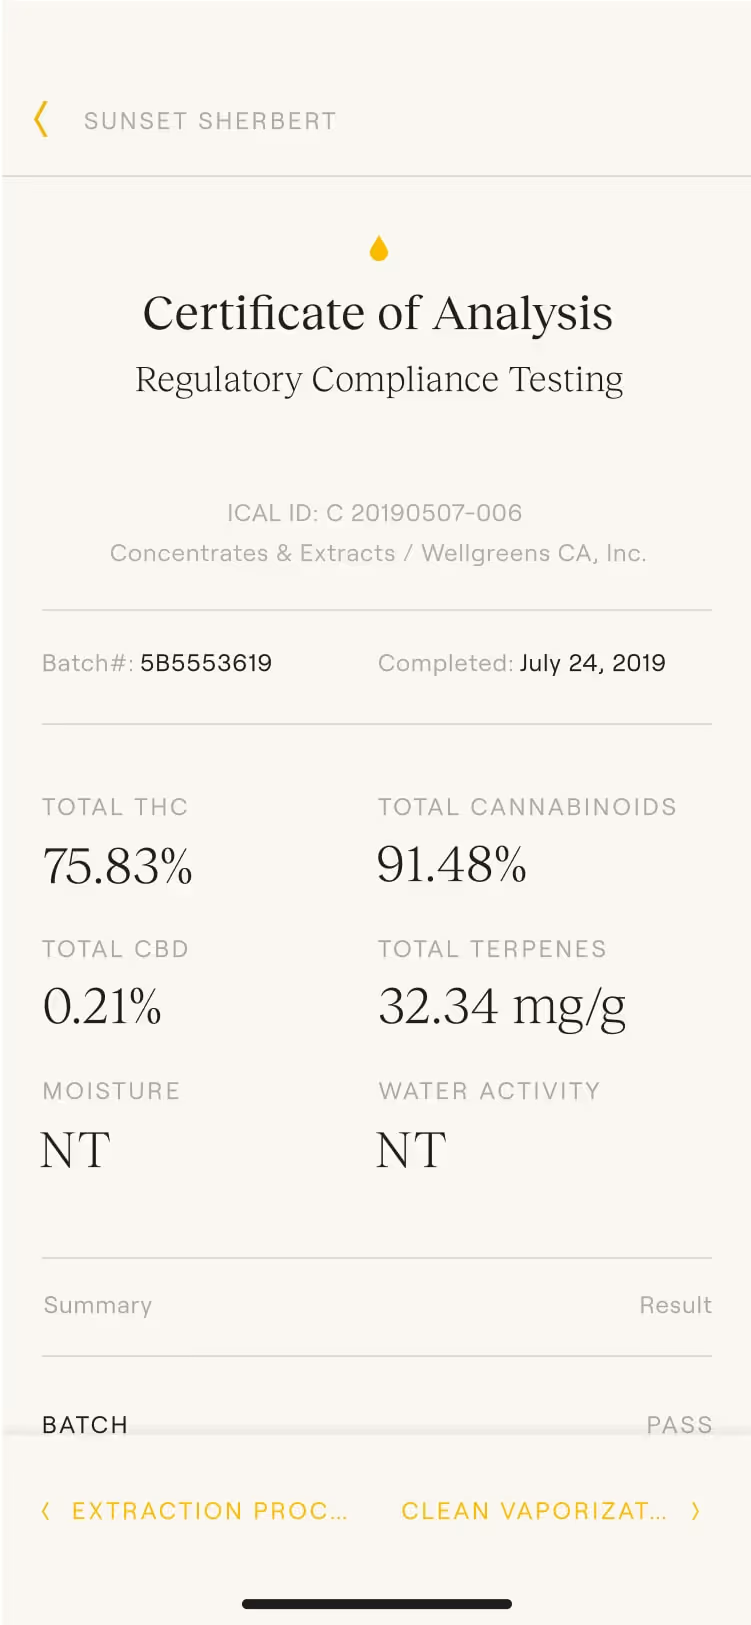

Airgraft

Selected Projects

Project images

Type

Services

Credits